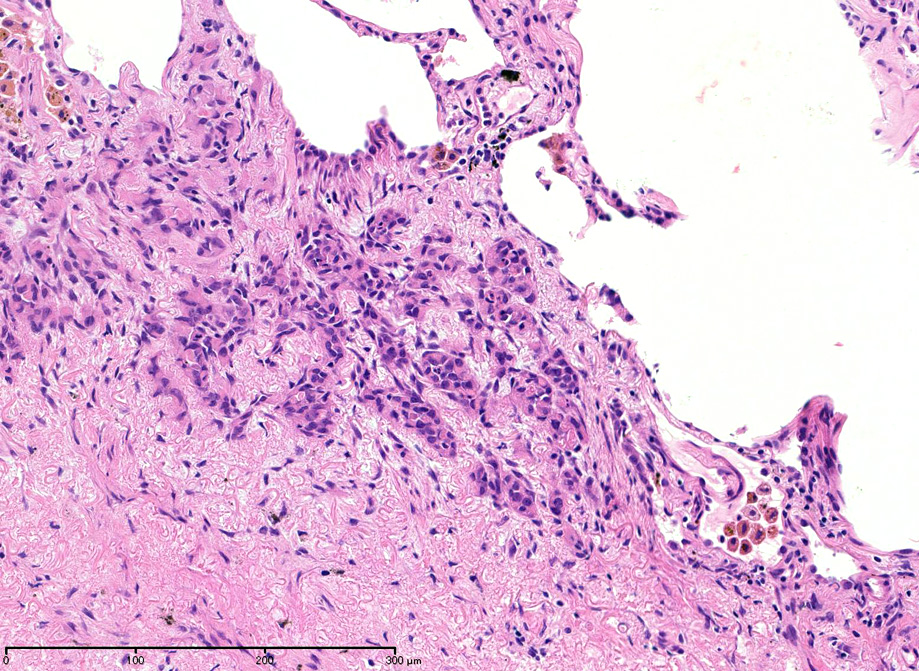

hyperchromaticな類円ないし多角の核で好酸性の広めの細胞質をもつ上皮様細胞が増殖している。右図では血管内を占拠するように腫瘍細胞が認められる。